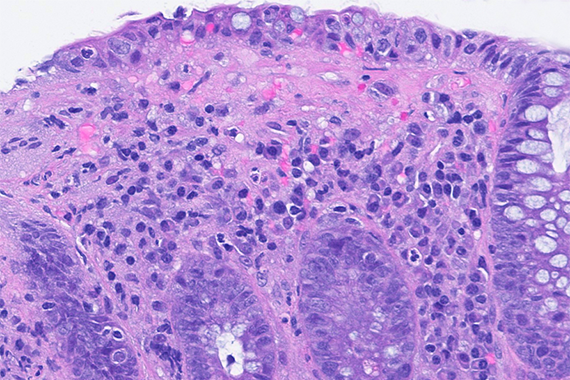

Ultrasound-guided biopsy of a pancreatic lesion in a 38-yeard-old woman (histological and cytological correlation).